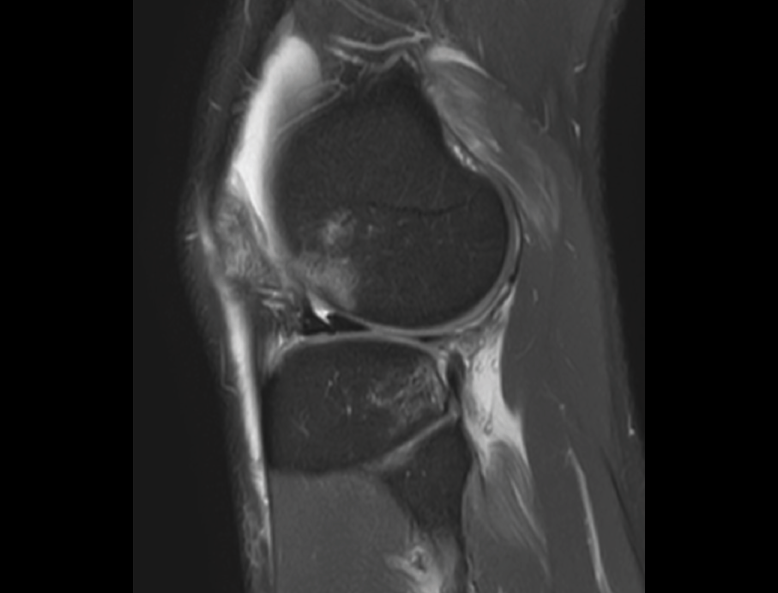

1.2.2. Ligamento cruzado anterior (LCA) (Figuras 40, 41, 42, 43 y 44)

Figura 40. Corte de secuencia sagital T2 Fat-Sat de resonancia magnética de rodilla: ligamento cruzado anterior normal.

Figura 41. Cortes de secuencia sagital T2 Fat-Sat de resonancia magnética de rodilla: rotura central del ligamento cruzado anterior.

Figura 42. Cortes de secuencia sagital T2 Fat-Sat: rotura proximal del ligamento cruzado anterior.